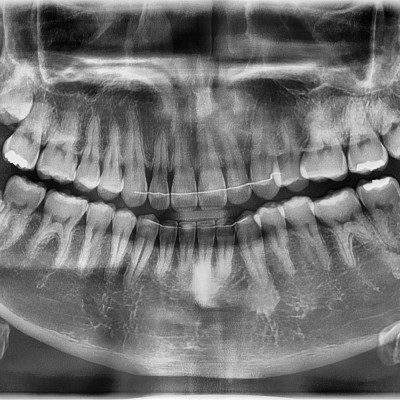

#18,28,38,48 사랑니 발치 #18,28,38,48 사랑니 발치 구강외과 전문의가 당일 발치했습니다.

작성자 이턱이 작성일 01-19 조회 37